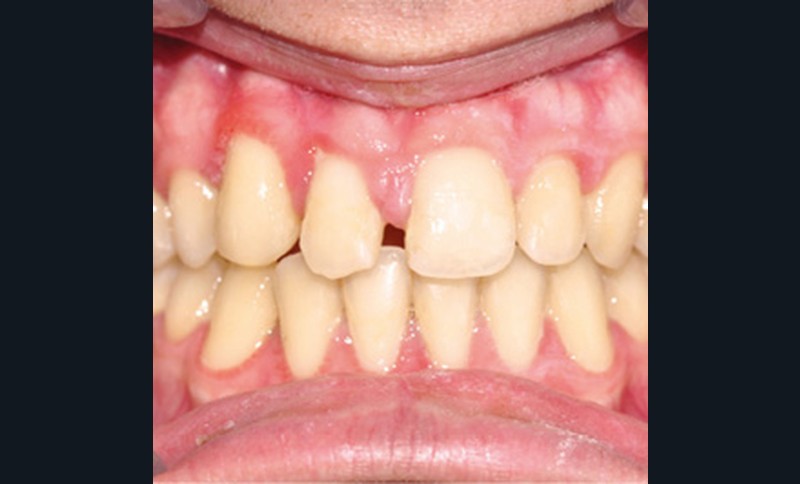

D’un point de vue occlusal, le patient, en denture adulte jeune stable, présente une classe II d’Angle bilatérale de 4 mm, associée à un encombrement maxillaire de 5 mm et mandibulaire de 2 mm. La face mésiale de 21 est centrée avec le plan sagittal médian, la non-concordance des médianes incisives est d’origine mandibulaire (déviation de la médiane mandibulaire vers la gauche) (fig. 1b-d).

Son incisive centrale supérieure droite (11) présente un défaut de structure amélaire sévère, compromettant une technique restaurative pérenne a minima. L’examen de la panoramique (fig. 1e) et de la radiographie rétroalvéolaire de 11 (fig. 1f) objective une fracture coronaire verticale, ainsi qu’une racine grêle et courbe, peut-être en rapport avec un ancien traumatisme [1]. Le rapport couronne clinique/racine clinique est défavorable.